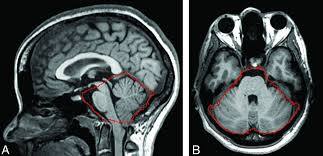

What tumours is MRI good for visualising, and what region of the brain is it good for visualising?

Soft tissue tumours

Good if PC is dizziness/ ataxia/ CN involvement - can see posterior fossa on MRI